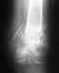

Поэтой одной проекции особых проблем не вино. Может, что-то не так на профильном снимке. Движения надо разрабатвать в любом случае.